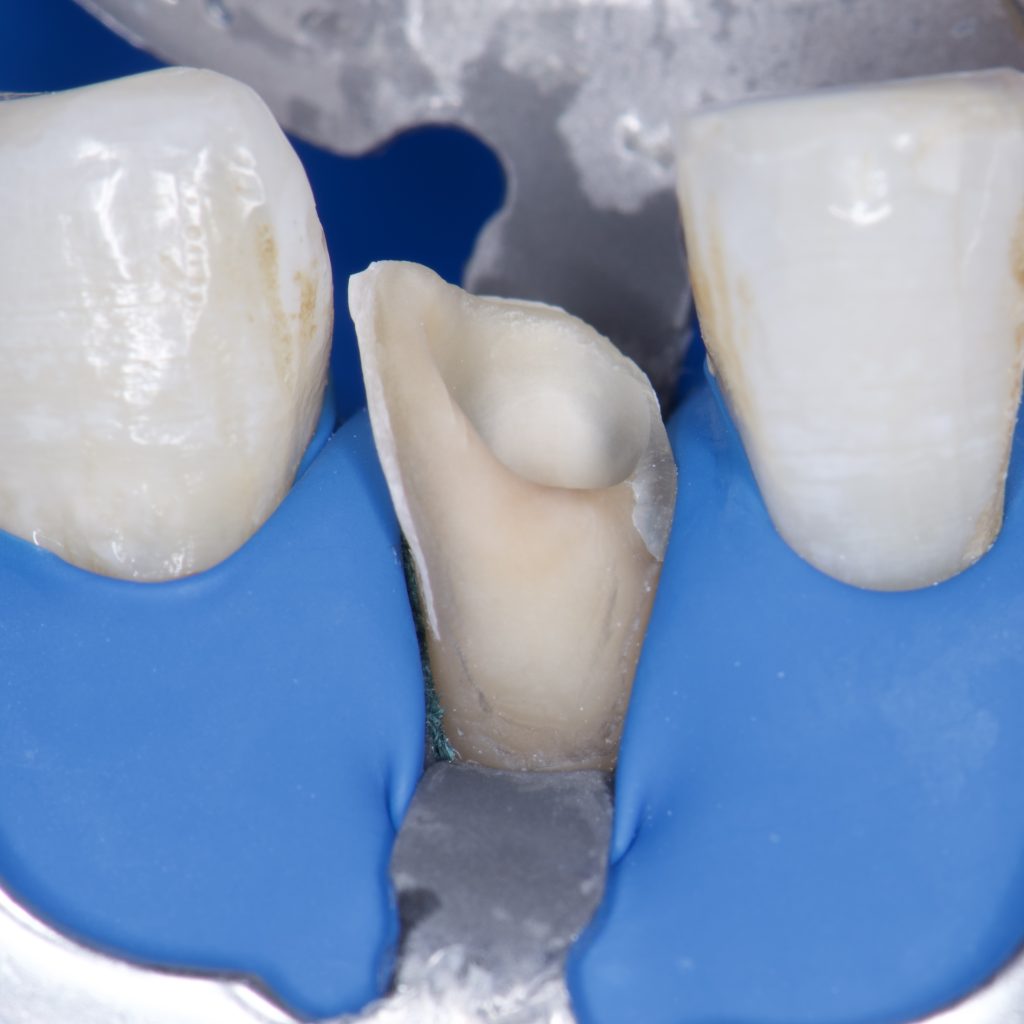

– Direct composite restoration, layering technique

1 month Follow up